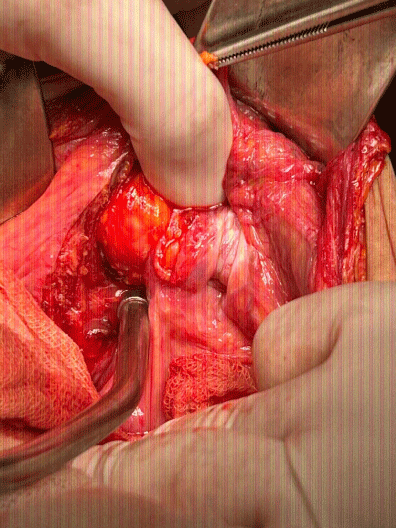

Intraoperatively, a Richter’s femoral hernia was identified on the right side [2,3]; containing a loop of small bowel with a 2 cm perforation located 40 cm from the ileocecal valve (Figure 1). Resection of the affected segment was performed with a primary end-to-end anastomosis. The hernia defect was repaired with a polypropylene mesh in a sublay position [4]. A Penrose drain was placed in the pelvic cavity. The patient tolerated the procedure well, with initial postoperative stability. However, during the postoperative course, she developed community-acquired pneumonia, requiring antimicrobial therapy. Despite appropriate management, the patient died 10 days postoperatively due to respiratory complications.

Figure 1: Intraoperative view showing distended small bowel and hernia sac protruding through femoral canal. View Figure 1